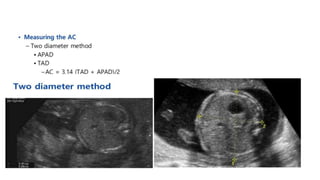

Abdominal Circumference

• The single most important measurement to make in late pregnancy. It reflects more of fetal size and weight

Abdominal Circumference • Thesingle most important measurement to make in late pregnancy. It reflects more of fetal size and weight rather than age. Serial measurements are useful in monitoring growth of the fetus.